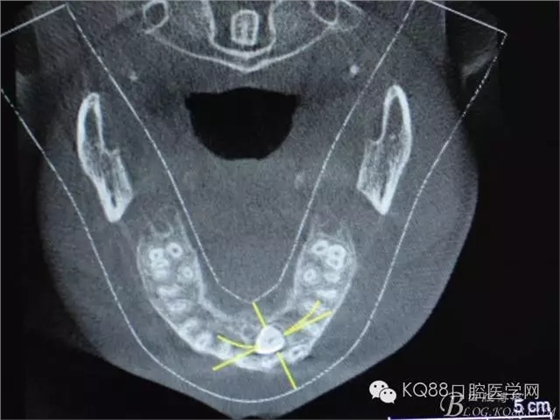

圖3.冠向切面:23牙冠緊鄰21的牙根

圖4.縱剖面顯示23位于腭側(cè)

圖5.水平切面觀23位于腭側(cè)